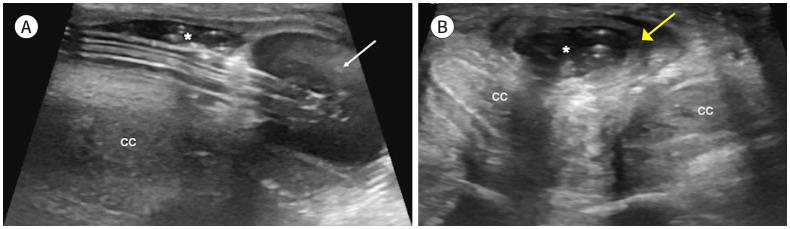

Penile emergencies are uncommon and can be categorized as having infectious, vascular, traumatic, or multifactorial etiologies. To facilitate early diagnosis and treatment during emergency, US and color Doppler imaging are imperative. US depicts hypoechoic collections regardless of the presence of air foci in infections like abscess and Fournier's gangrene. Color Doppler imaging is conducted to evaluate vascular conditions such as penile Mondor disease (PMD) and priapism. PMD is indicated by the absence of color flow and non-compressibility of dorsal penile vein. Priapism can be categorized based on cavernosal artery flow: high flow and low flow. In traumatic injuries like penile fracture, US reveals breach in tunica albuginea with hematoma. Peyronie's disease can be multifactorial in origin and the imaging is commonly visualized as thickening of the tunica albuginea and echogenic calcified plaques. Urethral injuries are urethral discontinuity with adjacent collection. Urethral calculus is visualized as echogenic focus with posterior acoustic shadowing. Therefore, effective collaboration between radiologists and urologists is required for appropriate initial diagnosis and prompt treatment.

阴茎急症并不常见,可分为感染性、血管性、创伤性或多因素病因。为便于在急诊时进行早期诊断和治疗,超声(US)和彩色多普勒成像必不可少。在诸如脓肿和福尼尔坏疽等感染中,无论是否存在气灶,超声均能显示低回声液性聚集。进行彩色多普勒成像以评估血管状况,如阴茎蒙多氏病(PMD)和阴茎异常勃起。阴茎蒙多氏病表现为阴茎背静脉无血流信号且不可压缩。阴茎异常勃起可根据海绵体动脉血流分为:高流量型和低流量型。在阴茎骨折等创伤性损伤中,超声显示白膜破裂并伴有血肿。佩罗尼氏病的病因可能是多因素的,影像学表现通常为白膜增厚和回声增强的钙化斑块。尿道损伤表现为尿道连续性中断并伴有相邻液性聚集。尿道结石表现为伴有后方声影的回声增强灶。因此,放射科医生和泌尿外科医生之间需要有效协作,以进行恰当的初步诊断和及时治疗。